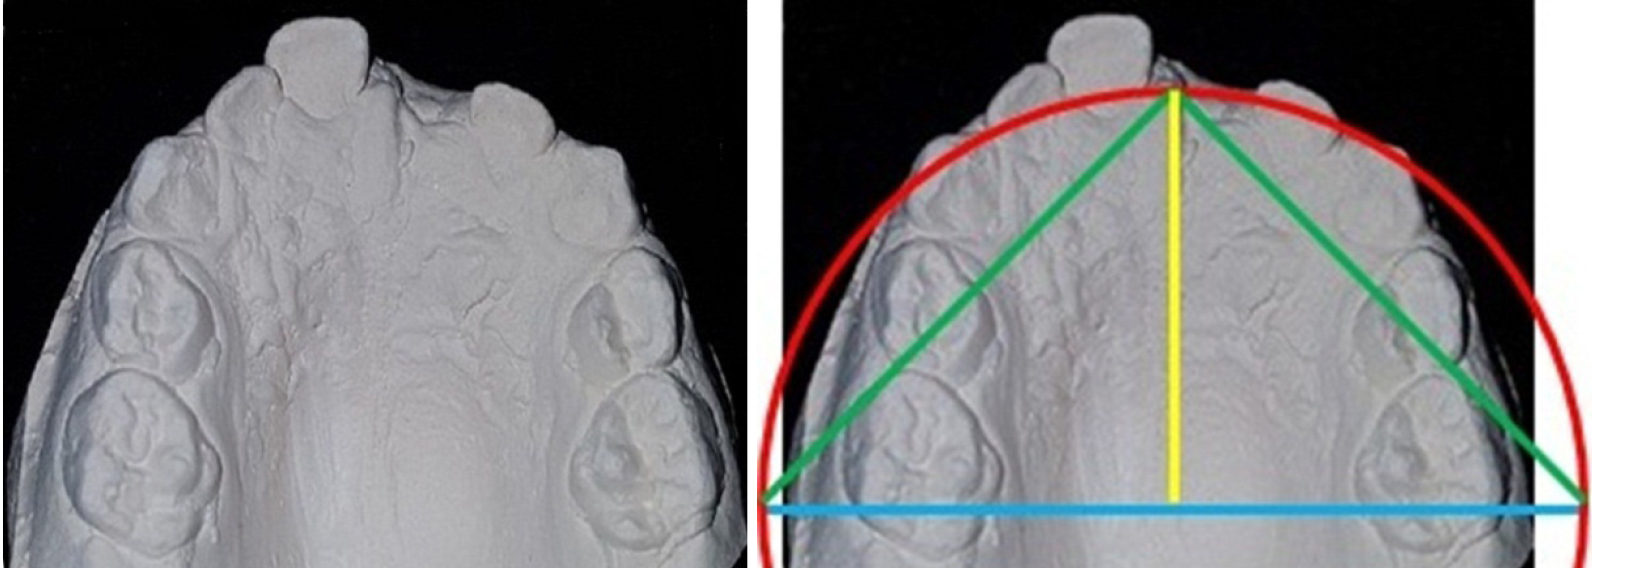

Таким образом, разработанные методы диагностики аномалий зубных дуг в трансверсальном направлении могут быть полезны врачам-ортодонтам, что представлено на клиническом примере. Полученные данные позволили сравнить размеры зубной дуги с прогнозируемой формой и ее графической репродукцией (рис. 1). При биометрии пациента 4 лет отмечалось сужение арки в области моляров и увеличение сагиттальных размеров, что подтверждено графическим построением арки и предполагаемым расположением центральной межрезцовой точки.

Рис. 1. Анализ гипсовых моделей при патологической форме зубных дуг